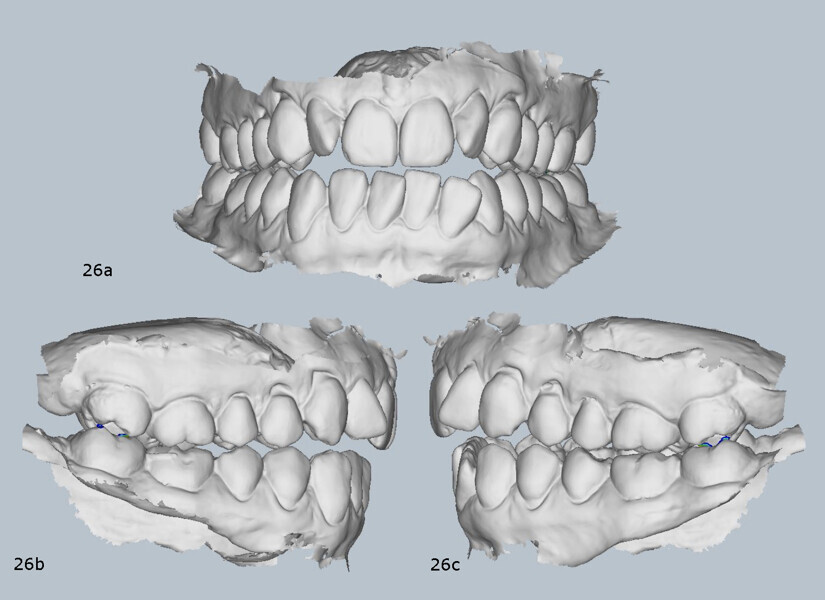

We selected a two-piece FACE splint, worn 24 hours a day in the posterior segment during the day and the anterior segment at night (Fig. 23). The splint therapy lasted for four months, during which a stable condylar position was achieved, the patient transitioned to a single arc of closure and full remission of TMD symptoms was obtained. As a result of mandibular posterior rotation, the occlusion changed, presenting with an increased anterior open bite (Fig. 24), an increased overjet (Fig. 25) and an increased Class II dental relationship (Fig. 26).

The post-treatment panoramic radiograph showed good root parallelism and no worsening of the pre-existing root resorption or periodontal condition (Fig. 32). The final cephalometric radiograph and tracing showed that, although the patient retained a Class II skeletal pattern, the values had improved owing to mandibular auto-rotation (ANB from 6.9° after splint therapy to 4.4° at the end of treatment). This auto-rotation had also improved the vertical measurements between the end of splint therapy and the end of treatment: maxillary inclination (SN–OP) had decreased from 18.6° to 16.2°, Ricketts’ facial axis from 92.7° to 91.4° and Jarabak’s sum of angles from 392.0° to 387.6° (Fig. 33).

Finally, and most importantly, orthopaedic stability had been achieved, and there was no discrepancy between maximum intercuspation and centric occlusion (Fig. 34). There was also complete resolution of the TMD symptoms.